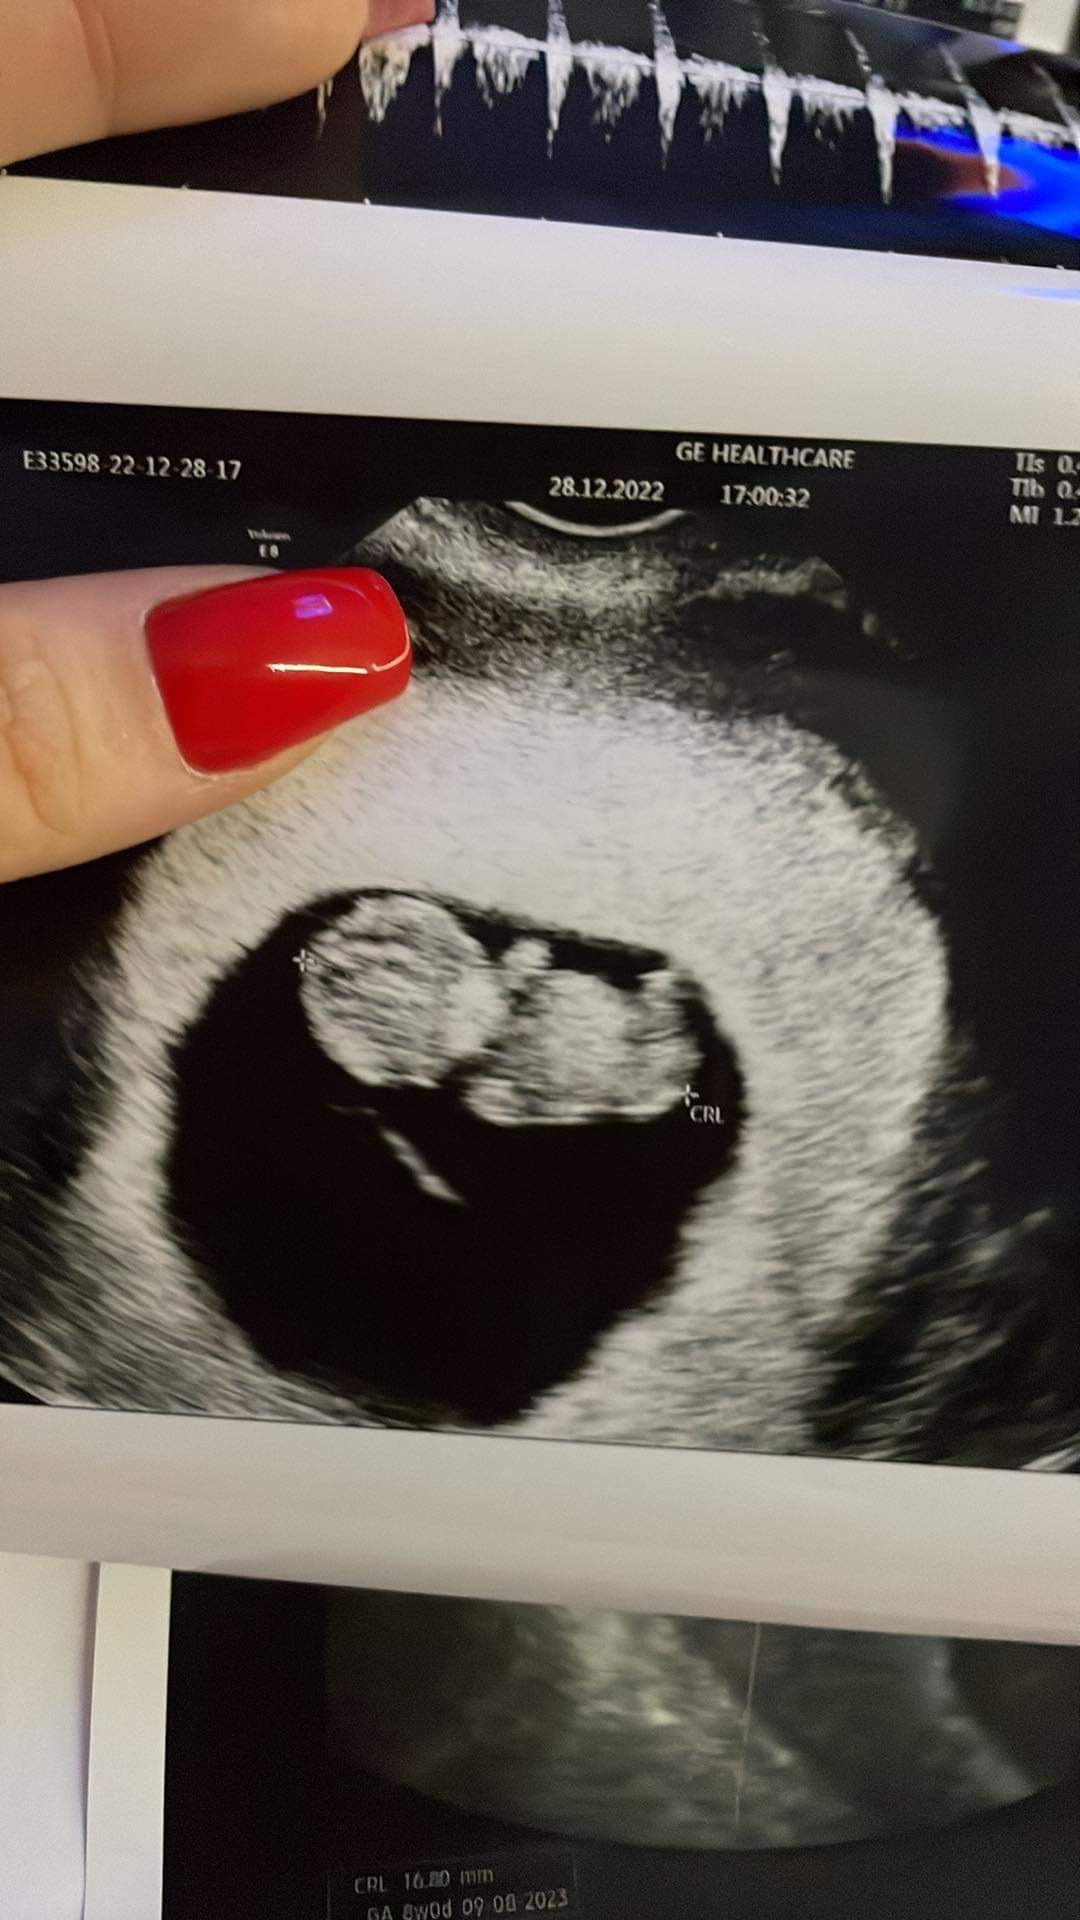

Cześć dziewczyny mam takie pytanie wczoraj miałam badanie usg ale ten lekarz który mnie wykonał źle zmierzył dziecko i wyszło na to że dziecko się nie rozwija bo dwa tygodnie miało tyle samo czyli 16,80mm wystraszona pojechałam do drugiego lekarza i zrobiłam kolejne usg czy to może zagrażać dziecku? po czym okazało się że dziecko ma już 27,1mm Nawet spójrzcie na zdjęcie pierwsze zdjęcie jest od pierwszego lekarza i nic tam nawet nie widać Dlatego martwi mnie czy dwa usg w jeden dzień nie zaszkodzą dziecku tym bardziej że mój chłopak pojechał kłócić się z tym pierwszym lekarzem i on powiedział że życzy mi powodzenia jak będę tak robić to skończe źle Ale naprawdę nie miałam wyjścia

• 827EC093-BFB9-464B-8050-39D5A6AAA93B.jpeg

827EC093-BFB9-464B-8050-39D5A6AAA93B.jpeg

190,3 KB · Wyświetleń: 135

No ja już mam tak naprawdę trzeciego lekarza i wczoraj co byłam u tego drugiegNo ja już mam tak naprawdę trzeciego lekarza i wczoraj co byłam u tego drugiego jest bardzo fajna u mnie 9 tydzień +5 wczoraj jak zobaczyłam już takiego bobasa popłakałam się wcześniej straciłam ciąże 7 lat temu bo zatrzymała się na 6 tygodniu